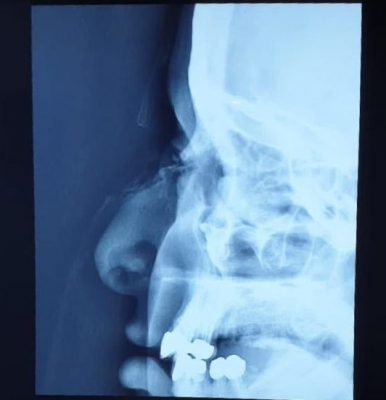

وأوضح الفريق الطبي أن المصابه حضرت للمستشفى في حالة حرجة بعد فقدها كمية كبيرة من الدم نتيجة تعرض الأنف لكسر مضاعف وعميق بسبب الجسم الحاد الذي سقطت عليه ، وتم تقديم الأسعافات الأولية التي أوقفت النزيق وعمل الفحصوات المخبرية والأشعة المقطعية لها والتي اكدت وجود تهتك شديد وكسر مضاعف في عظام الانف وغضاريف الانف مع فقدان للجلد وجرح عميق استدعى تدخل جراحي طارئ وأدخلت على أثرها لغرفة العمليات وعمل ترميم لانسجة الانف وتعديل للكسر العظمي وترقيع تجميلي للجلد المفقود من الانسجه المجاوره ووضع دعامه خارجيه وداخليه لحمايه الانف ، ليتم بعدها متابعة المريضة في أقسام التنويم حتى خروجها من المستشفى بصحة جيدة ولله الحمد .